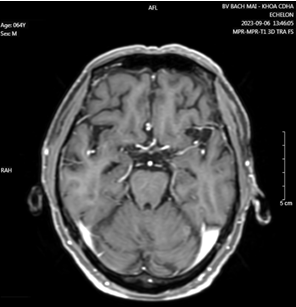

Cộng hưởng từ sọ não có tiêm thuốc đối quang từ: